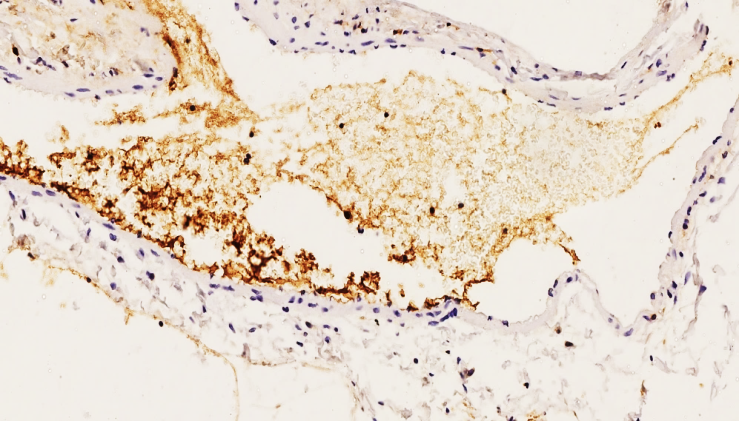

Thus, in our group 2, the expression of the CD 63 marker in 45-59-year-olds was detected in granular deposits formed by platelet aggregation in thrombi in 13 out of 26 cases (61.9%), confirming the quiescence of the vascular endothelium and the sharp decrease in the response of the vascular inner surface to any damage. In 3 out of 11.54% of cases, the CD 63 marker was found to be moderately and lowly positive on the vascular endothelium surface in 45-49-year-olds, which also confirms the existence of critical age-related transition points in the age boundaries of the transitional group 2. | Figure 9. Group 2. 51-year-old woman. Positive expression of thromboplastins in the form of adhesive granular thromboplastins in the vascular lumen. No changes in the vascular endothelium are detected. Staining is Dab chromogenic. Size 20x10 |

That is, among the 18-44 and 45-59-year-olds, the degree of damage in the 41-44 and 45-49-year-olds is close to each other, which confirms the fact that the vascular reactivity is close to each other, and after the age of 50, these indicators decrease sharply.In 10 of our group, low and negative expression of the SD 63 marker was detected, totaling 38.46%. This also confirms our above-mentioned ideas, and the presence of granular adhesive thromboplastins in the migrated thrombus is mainly characterized by the presence of endothelial cells on the surface of the vascular intima. | Figure 10. Group 2. 49-year-old woman. Moderate positive expression of the CD 63 marker is detected in the thrombus in the vascular lumen and in granular platelets adhered to the vascular wall. Focal changes are detected in the vascular endothelium. Staining Dab chromogenic. Size 20x10 |

Thus, in group 2, the positive reaction of the CD 63 marker is 1.5 times lower than in group 1, and the complication of thromboembolism is that vascular damage occurs mainly due to migrated thrombi, and in acute thromboembolism, the presence of thrombi in the vascular lumen and various secretory active secretions of the endothelium in response to them were detected in 11.54% of 26 cases. This means that in various types of vascular embolism, there is a decrease in active secretion from the endothelial cells and an age-related decrease in vascular response, and an increase in vascular resistance. This confirms the involutive manifestation of biological aging in the age-related endothelium of the vessels.Clinically, morphologically, it is also proven that with age, in various thromboembolic syndromes, vessels become more fragile and prone to damage, mainly due to foreign thrombi in the vascular lumen and a very small amount of biologically active substances are produced on the inner surface of the vessel.In our next group, it is found that the mortality rate from thromboembolic complications is lower than in group 2, manifested by the retention of thrombi in areas of migration and an age-related decrease in the local response of the vessels. | Figure 11. Group 3. 74-year-old woman. Massive obturating pulmonary artery anterior wall thrombus, massively adhered granular platelets in the thrombus, high positive expression of the CD 63 marker. Staining is Dab chromogenic. Size 20x10 |

In particular, in our group 3, out of 26 cases from 60-74 years old, moderate positive expression of the CD63 marker was detected in 8 cases (31.13%), mainly in platelets that underwent massive granular adhesion in the thrombus in the vascular lumen, indicating that the thrombus adhered directly to the vascular wall, and Weibel-Palade bodies were almost not detected in the endothelial cells on the inner surface of the vascular wall.This indicates a decrease in the response of the endothelium to acute injuries, as well as a sharp decrease in the von Willebrand factor. This is also clinically morphologically due to age-related biological aging in the body, as a result of a sharp decrease in water, a decrease in the ability of endothelial cells to produce biologically active substances, including a critical decrease in the content of granular vesicles that bind the CD 63 marker, von Willebrand factor, and P-selectin (see Fig.10-11).In this 3rd group, a total of 18 CD 63 markers showed negative expression in relation to the inner surface of the vessel, while moderate positive expression was detected in relation to migrated thrombi. This is explained by the fact that platelets in the composition of the migrated thrombi were mainly detected in granular adhesive protein molecules.So, in group 3, among 60-74-year-olds, 8 out of 26 cases in 31.13% had medium positive expression of the SD 63 marker, 18 had low positive reaction in 69.23%, and medium positive expression in thrombi. The expression of this SD 63 marker was obtained mainly in relation to the vessel, excluding granular adherent platelets in the migrated thrombi, and the positive reactions were mainly attributed to the content of the thrombus. This confirms that the level of positive expression of the SD 63 marker in 60-74-year-olds decreased by 2.45 times compared to 18-44-year-olds, and by 1.54 times compared to 45-59-year-olds.